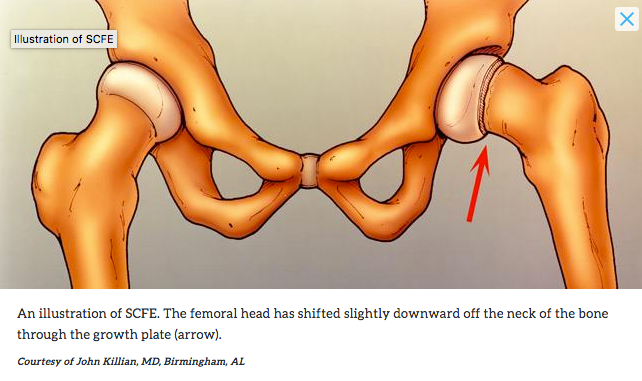

2. As ‘n groeiende kind kla van knie- of bobeenpyn, en daar is nie fout by die knie of bobeen nie, moet die kind se heup ondersoek word, want die bobeen-kop wat in die heuppotjie moet pas, kan verbrokkel, of selfs afbreek.

Lees meer: https://orthoinfo.aaos.org/en/diseases–conditions/slipped-capital-femoral-epiphysis-scfe